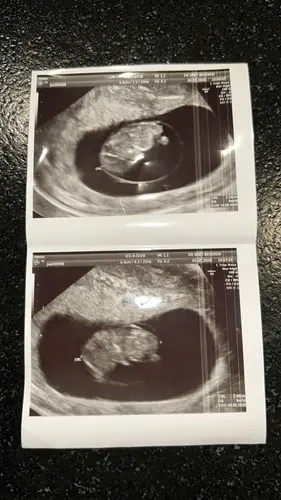

8w 🤩

Is van 7weken en 2 dagen Nu 9 weken